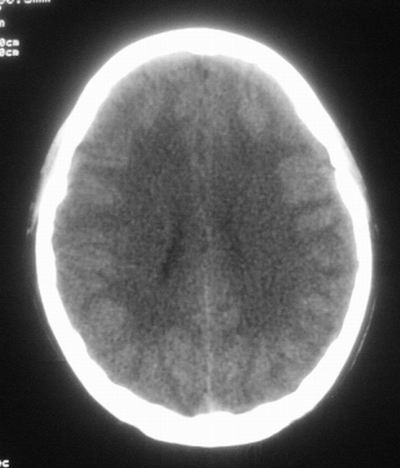

治疗三天后复查ct片示:

治疗三天后复查ct:除左侧额顶叶血肿外。左侧额叶另见片状低密度灶,密度不均匀,境界不清;考虑脑梗塞。